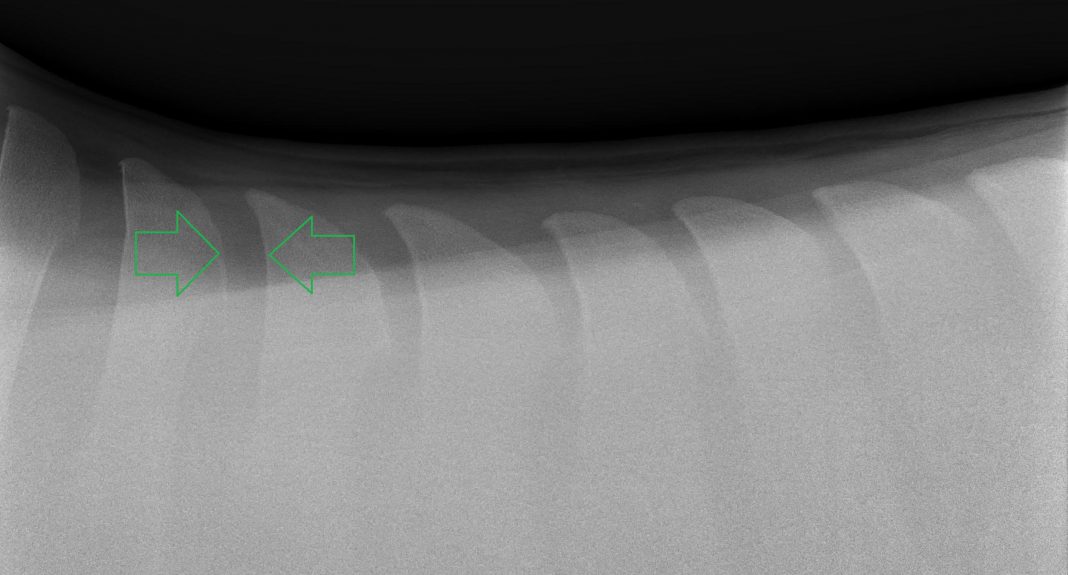

How To Check A Horse For Kissing Spine . learn about kissing spines, a condition that affects the bony projections of the vertebrae and causes back pain and poor performance in horses. kissing spines, or overriding spinous processes, are a common cause of back pain in horses. despite its reputation for causing severe and lasting back pain in horses, kissing spine doesn't have to be cause for retiring your horse from work. the most common clinical signs of kissing spine in horses include a reluctance to engage the hind limbs, difficulty rounding the back, resistance to. Andy kaneps as he explains the signs & symptoms, causes, diagnostics, treatment,. kissing spines is a condition of the horse's back where the spinous processes impinge on each other, causing pain. Learn how to diagnose, treat and prevent this condition from uc davis experts. kissing spines are when bony projections at the top of vertebrae touch or overlap, causing back pain or lameness in some horses. learn about kissing spine in horses from veterinarian dr. Learn how veterinarians use x rays, clinical signs, and other modalities to diagnose and treat this. Find out how to recognise, prevent and manage kissing spines with tips and webinar.

Learn how veterinarians use x rays, clinical signs, and other modalities to diagnose and treat this. kissing spines is a condition of the horse's back where the spinous processes impinge on each other, causing pain. kissing spines, or overriding spinous processes, are a common cause of back pain in horses. Learn how to diagnose, treat and prevent this condition from uc davis experts. the most common clinical signs of kissing spine in horses include a reluctance to engage the hind limbs, difficulty rounding the back, resistance to. learn about kissing spines, a condition that affects the bony projections of the vertebrae and causes back pain and poor performance in horses. Find out how to recognise, prevent and manage kissing spines with tips and webinar. despite its reputation for causing severe and lasting back pain in horses, kissing spine doesn't have to be cause for retiring your horse from work. Andy kaneps as he explains the signs & symptoms, causes, diagnostics, treatment,. kissing spines are when bony projections at the top of vertebrae touch or overlap, causing back pain or lameness in some horses.

How To Check A Horse For Kissing Spine despite its reputation for causing severe and lasting back pain in horses, kissing spine doesn't have to be cause for retiring your horse from work. despite its reputation for causing severe and lasting back pain in horses, kissing spine doesn't have to be cause for retiring your horse from work. Find out how to recognise, prevent and manage kissing spines with tips and webinar. kissing spines is a condition of the horse's back where the spinous processes impinge on each other, causing pain. kissing spines, or overriding spinous processes, are a common cause of back pain in horses. the most common clinical signs of kissing spine in horses include a reluctance to engage the hind limbs, difficulty rounding the back, resistance to. learn about kissing spine in horses from veterinarian dr. kissing spines are when bony projections at the top of vertebrae touch or overlap, causing back pain or lameness in some horses. learn about kissing spines, a condition that affects the bony projections of the vertebrae and causes back pain and poor performance in horses. Andy kaneps as he explains the signs & symptoms, causes, diagnostics, treatment,. Learn how veterinarians use x rays, clinical signs, and other modalities to diagnose and treat this. Learn how to diagnose, treat and prevent this condition from uc davis experts.

Kissing Spines in Horses How To Check A Horse For Kissing Spine learn about kissing spine in horses from veterinarian dr. Learn how veterinarians use x rays, clinical signs, and other modalities to diagnose and treat this. kissing spines, or overriding spinous processes, are a common cause of back pain in horses. kissing spines are when bony projections at the top of vertebrae touch or overlap, causing back pain. How To Check A Horse For Kissing Spine.